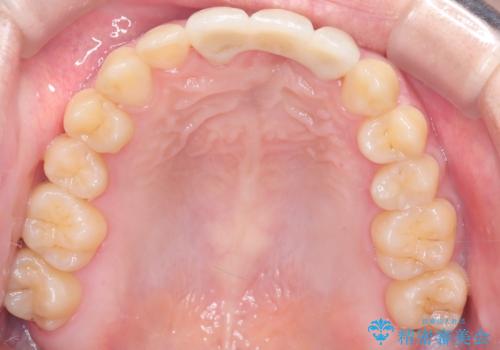

前歯の開咬とシザーズバイトを改善|インビザライン矯正

- 前歯が噛み合わない(開咬)ことと、奥歯の噛み合わせが交叉している(シザーズバイト)ことを改善するため、インビザラインによるマウスピース矯正を計画しました。精密な口腔内スキャナーを用いたシミュレーションで歯の移動経路を確認し、効果的な治療計画を立案。奥歯の咬合関係を整え、前歯の咬合を確立することを目指し、約1年半〜2年で治療を完了する予定としました。

前歯が噛まないため咀嚼が困難で、シザーズバイトにより噛み合わせに不調を感じていました。インビザラインを用いて、透明なマウスピースによる目立ちにくい矯正治療を実施。奥歯のシザーズバイトを改善した後、前歯の歯列を緻密に調整し、噛み合わせを整えました。定期的なマウスピース交換を通じて徐々に歯列が改善され、治療終了後には前歯が正常に咬合するようになり、噛み合わせの機能性と審美性が共に向上しました。